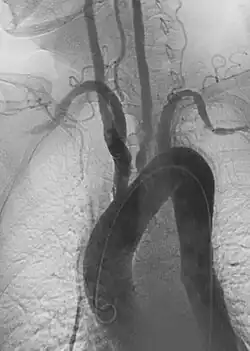

• Endovascular aneurysm repair: Placement of endovascular stent-graft across an aneurysm to prevent expansion or progression of the defective vessel.[6]

1. Aortic aneurysms include thoracic, abdominal and thoracoabdominal aneurysms. Treatment strategies are customized depending on the location, size, rate of growth and extent of the aneurysm as well as the medical comorbidities of the patient. For example, an intact, small but slowly growing aneurysm may be safely monitored with serial imaging for months or years before elective repair is considered. Elective endovascular aortic grafting is now routinely attempted when possible. Endovascular aortic repair (EVAR) refers to treatment of an abdominal aortic aneurysm, while thoracic endovascular aortic repair (TEVAR) is performed on the thoracic aorta. A ruptured aneurysm may be taken emergently for open, endovascular or combination repair.